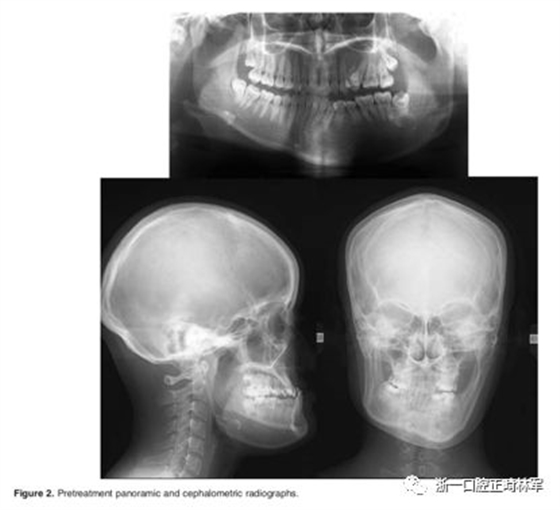

l 临床检查:口外相示:凹面型,严重面部不对称。口内相示:双侧磨牙III类关系,前牙反合,覆盖-3mm,覆合5mm,双侧侧方咬合角度有差异。影像学检查示:4颗第三磨牙阻生,左下第二前磨牙根部弯曲,右侧下颌偏斜18mm,左侧髁突增生,上唇、上颌咬合平面向右倾斜,大量的牙槽骨代偿,咬合平面向右侧倾斜3°,Go-Go'线向右倾斜12°,上颌中线右偏3mm,下颌中线右偏7mm,左侧下颌管靠近下颌骨下部边缘,骨性III类,ANB角-8.9°,下颌平面角15.4°。

下颌运动描记(MKG)显示,双侧下颌关节在张闭口时均向前滑动,运动轨迹稳定。左侧髁突形态使用Tc-99m羟基二膦酸盐骨扫描进行摄片记录。